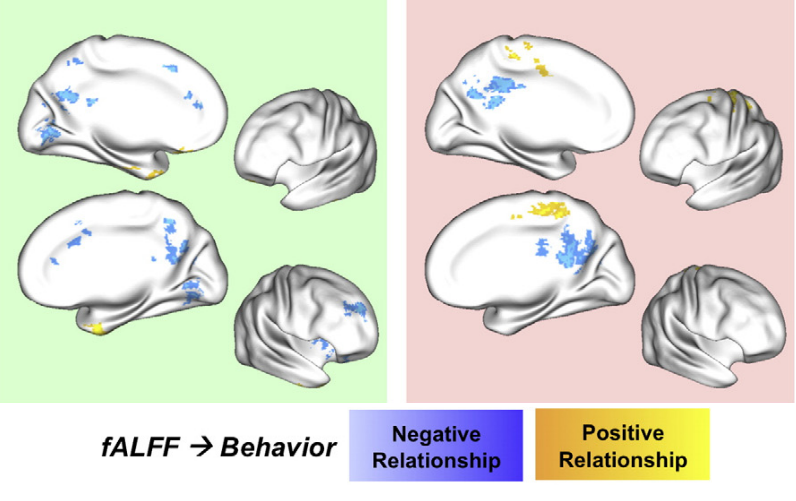

Methods: effect of CVR on fMRI

Results were thresholded at \(p<0.05\) after controlling for false discovery rate³

(then at \(p<0.001\) uncorrected)

1. Chen et al. 2013 (Neuroimage); 2. Golestani et al. 2016 (NeuroImage); 3. Benjamini et al. 2006 (Biometrika)

We used 3dLMEr¹ to set up the following LME models voxelwise (R syntax):

- \(RSF \sim cvr + (cvr|session) + (cvr|subject)\)

- \(tIA \sim RSF + (RSF|session) + (RSF|subject)\)

- \(tIA \sim cvr + (cvr|session) + (cvr|subject)\)

We used the first model considering the average GM value of RSF and CVR²

- \(RSF \sim cvr + (cvr|session) + (cvr|subject)\)

- \(tIA \sim RSF + (RSF|session) + (RSF|subject)\)

- \(tIA \sim cvr + (cvr|session) + (cvr|subject)\)

Results: CVR and RSF

Results: CVR and RSF

Results: CVR, RSF, and tasks

The relationship between CVR, RS fluctuations, and tIA

might be highly subject specific

or absent altogether.

- We did not observe a statistically significant effect of CVR on RS fluctuations, or of CVR and RS fluctuations on task induced activity, most probably due to the high variability between subjects

-

The failure of generalisation of previous observations might be related to different methods, but whether this is related to a better denoising and signal quality or to a possibly non optimal setting (e.g. compared to gas challenges) is uncertain

-

A different statistical perspective (i.e. Bayesian) is required to exclude any relationship between CVR and RS fluctuations, and further analyses are required to improve the agreement between CVR and RS fluctuations